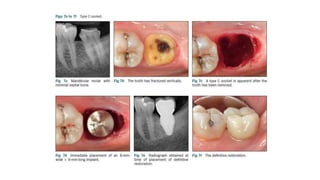

Classification Of Molar Extraction Sites For Immediate Dental Implant

Classification of molar extraction sites for immediate dental implant www.linkedin.com